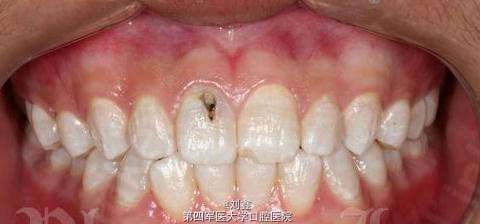

患者男 23岁,学生,目标是做一名主持人,但是因从小家乡水质不好,所以形成了氟斑牙,要求铸瓷贴面修复。

11有深龋,氟斑牙